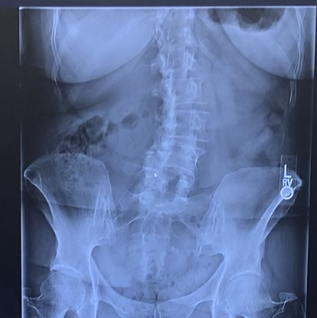

My hip was hurting for well over a year. It got to the point that I wouldn’t walk with my husband or X-Country ski anymore.

Dr. Carli replaced the joint and I am back to all activities. Wonderful!